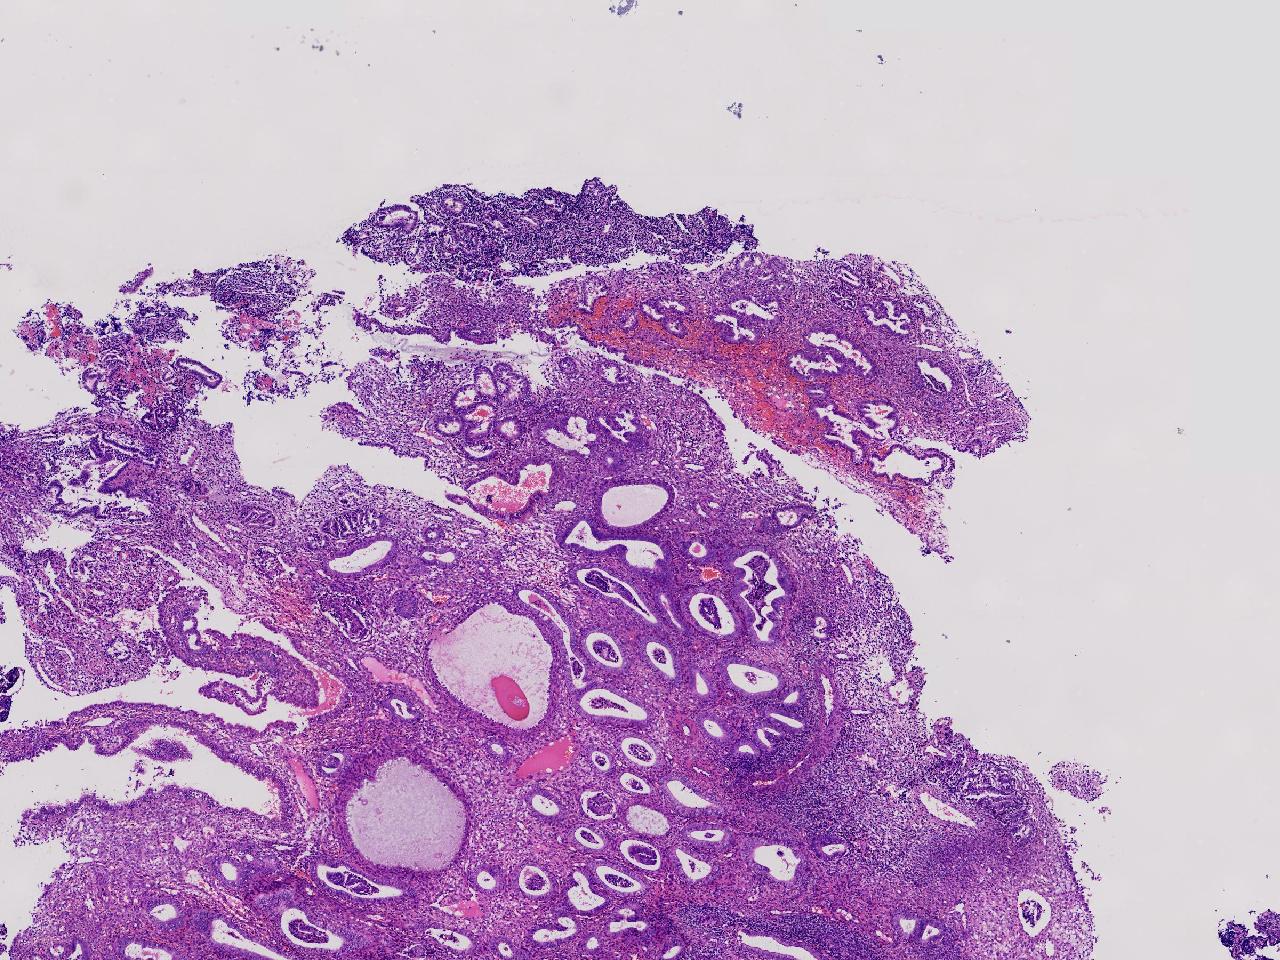

性别

女

年龄

55岁

女,55岁,月经紊乱4年,彩超示:子宫内膜增厚(内膜厚15.7mm),末次月经:2025年7月27日。

标本名称

宫腔镜下子宫内膜活检

大体所见

灰粉色不整形软组织多块,1.5X0.8X0.6厘米。

考虑:子宫内膜增生伴子宫内膜炎

子宫内膜增生紊乱,内膜息肉样结构